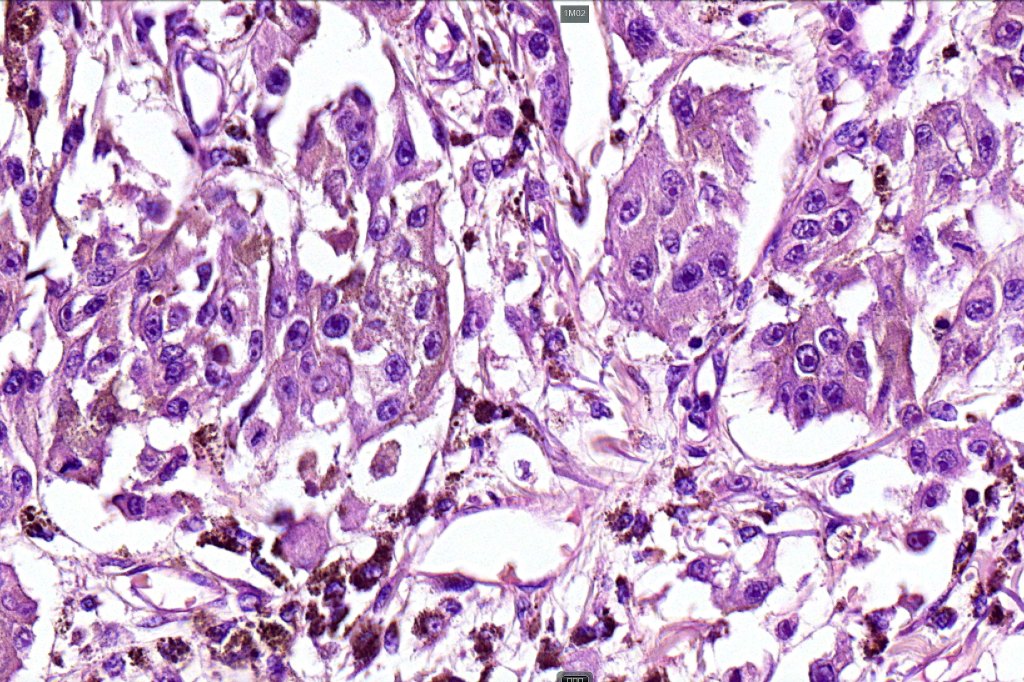

•Or melanoma showing admixed blue nevus-like features (dendritic cells and melanophages) in the absence of a precursor lesion

•Nuclear pleomorphism with prominent nucleoli, mitotic activity & abnormal mitoses

•Necrosis sometimes present